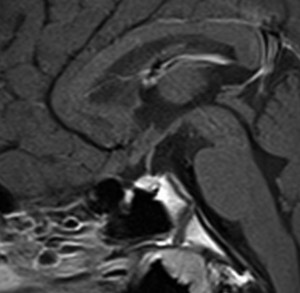

上のMRIで視神経交叉が腫大しているのが解りますが,下のMRI CISS画像では更に明らかです,左右の視神経と視交差と視索が腫大していました。視力を計ったら,右0.6,左1.5でいびつな視野欠損がありました。腫瘍はのう胞形成しながら左の視床下部から大脳基底核にも浸潤していました。

6年以上発ちますが再発はありません。右の画像のように視神経交叉のサイズは正常化しました。下垂体は左に偏っているので,おそらく右側の下垂体にも腫瘍があったのでしょう。汎下垂体機能低下症はありますが,副腎皮質ホルモンの補充は必要なくて,部分的下垂体機能低下症です。この幼児期の低身長が視床下部性であったのか,下垂体前葉機能低下によるものであったのかは不明です。治療後に高ナトリウム血症になる傾向があり,思春期早発症のために成長ホルモンを使用しながらLH-RHアナログを使うという事もしていますから,おそらく視床下部性のGHDであったのでしょう。